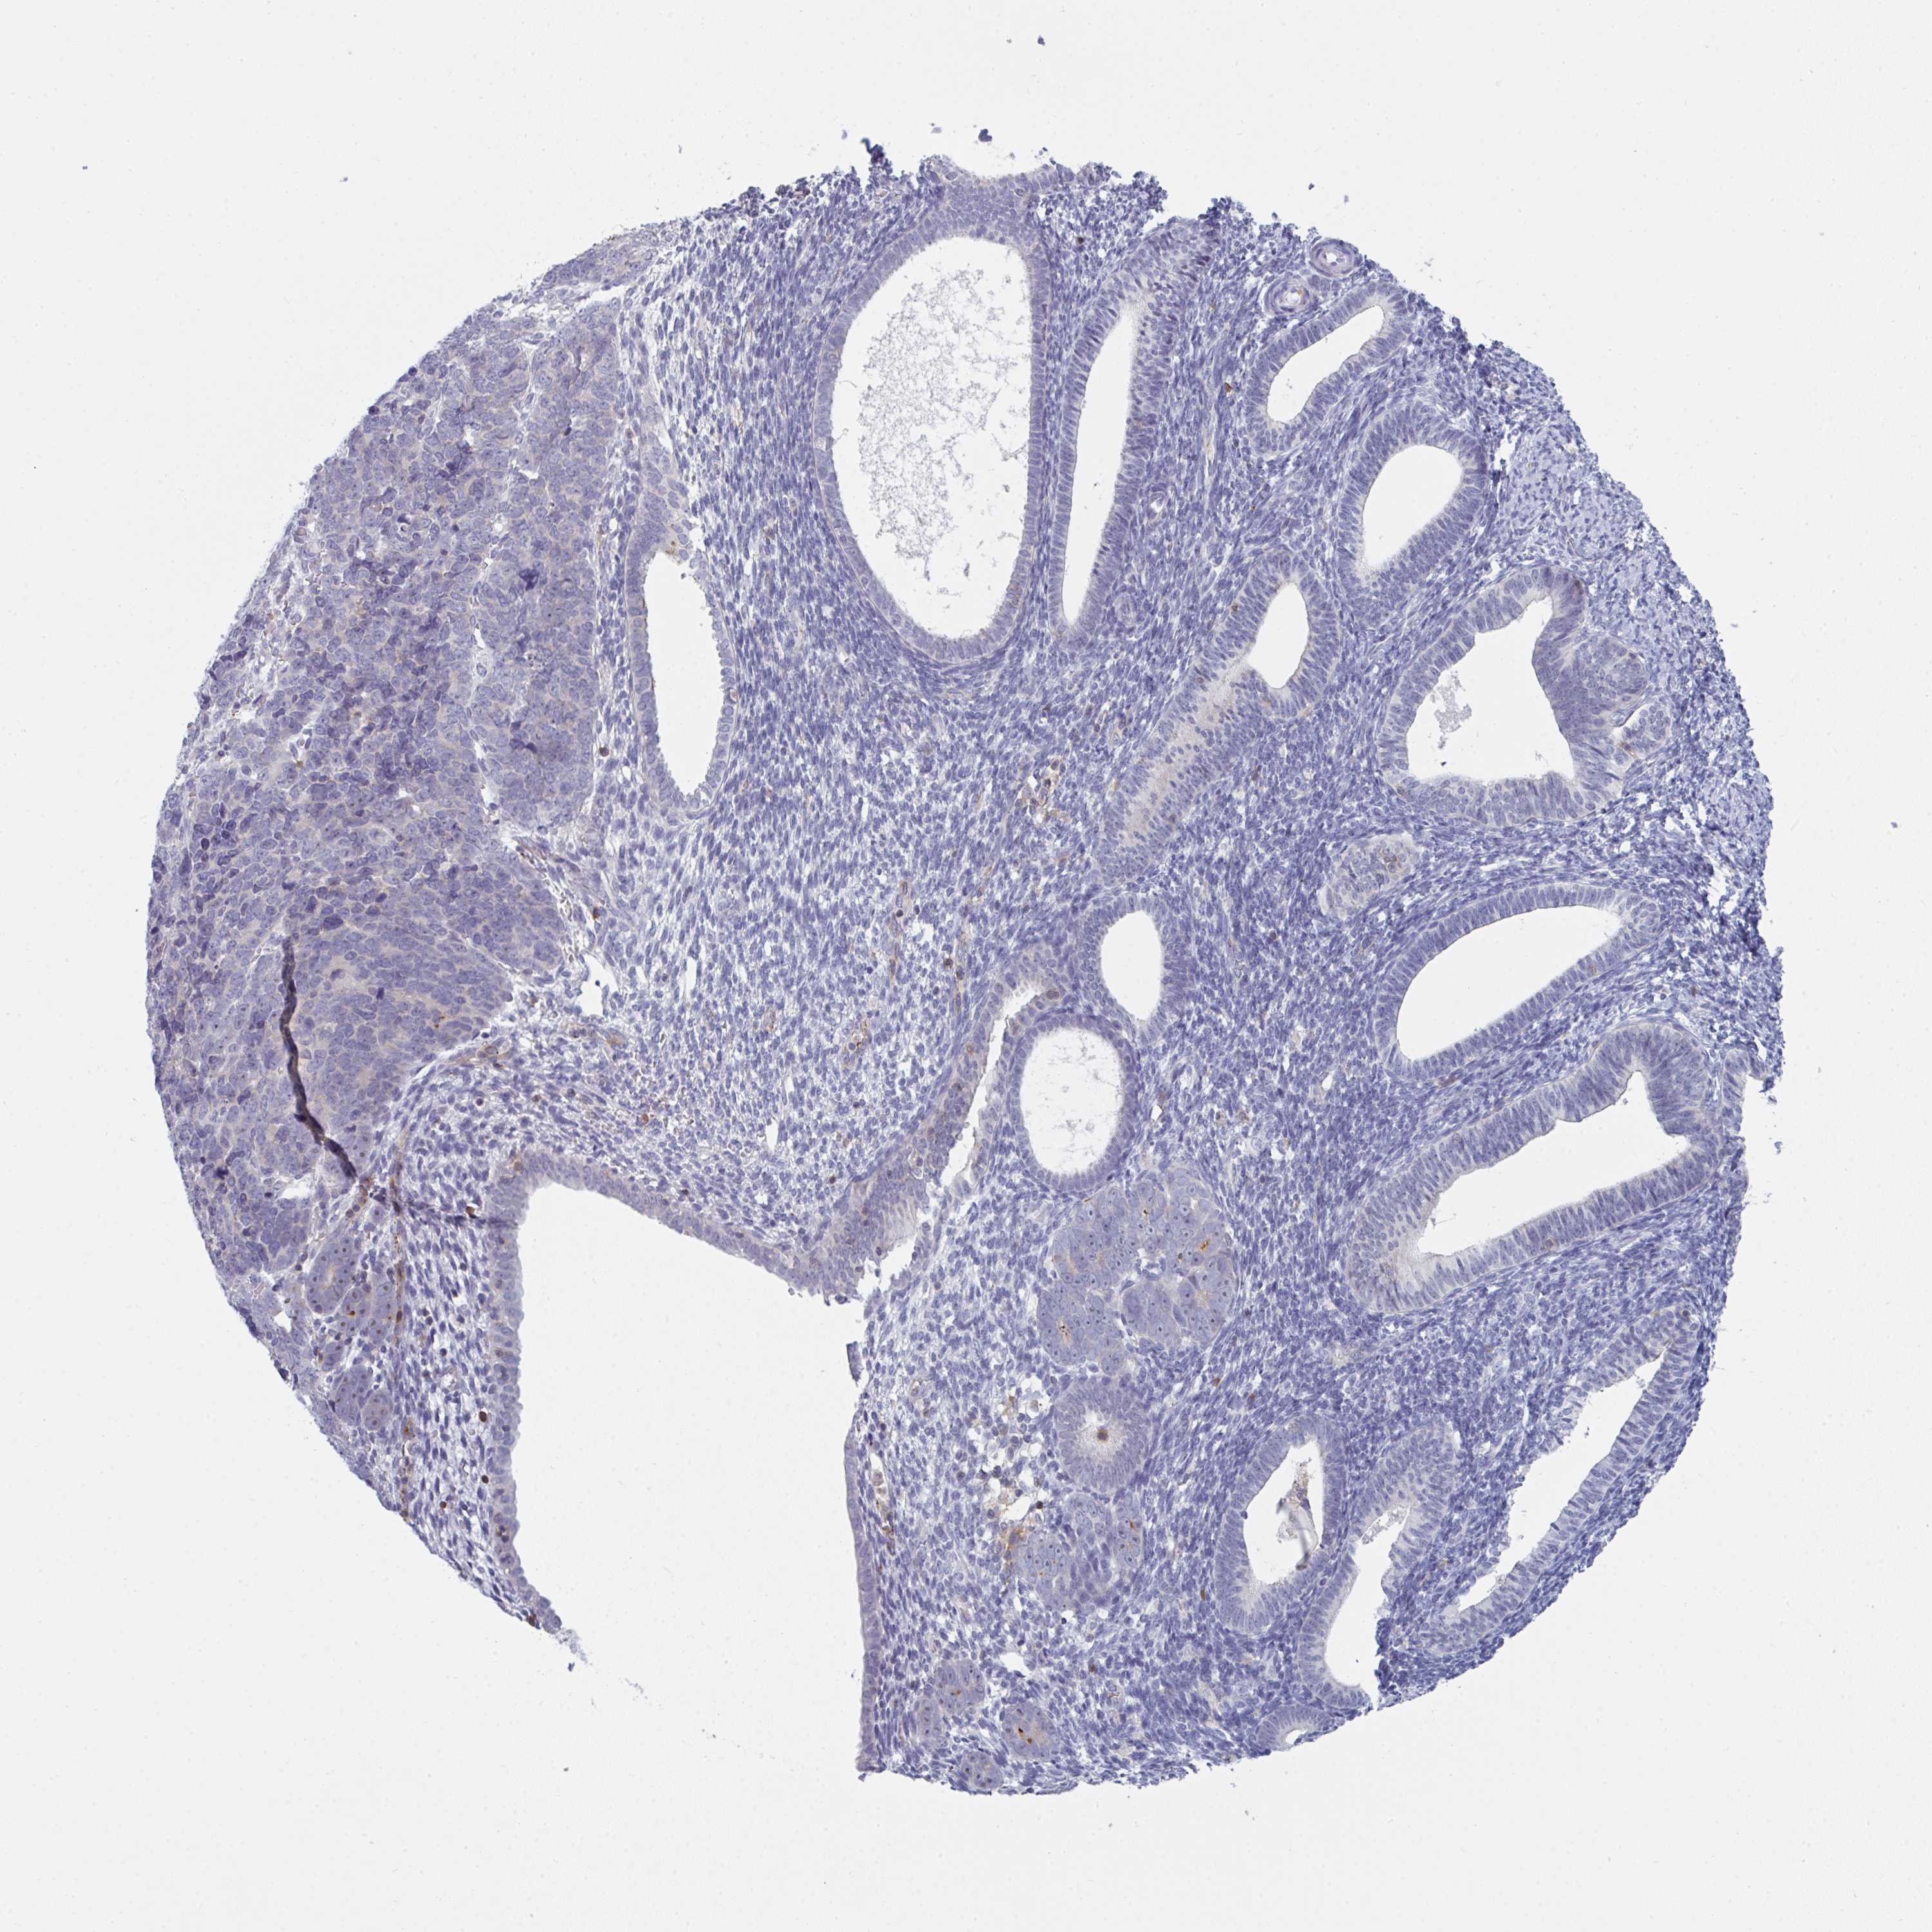

ENDOMETRIAL CANCER - Protein expressioni

A mouse-over function shows sample information and annotation data. Click on an image to view it in a full screen mode. Samples can be filtered based on level of antibody staining by selecting one or several of the following categories: high, medium, low and not detected. The assay and annotation is described here.

Note that samples used for immunohistochemistry by the Human Protein Atlas do not correspond to samples in the TCGA dataset.

Antibody stainingi

Antibody staining in the annotated cell types in the current human tissue is reported as not detected, low, medium, or high, based on conventional immunohistochemistry profiling in selected tissues. This score is based on the combination of the staining intensity and fraction of stained cells.

Each image is clickable and will lead to virtual microscopy that enables deeper exploration of all samples and also displays staining intensity scores, fraction scores and subcellular localization as well as patient and tissue information for each sample.

Antibody HPA050092

Antibody CAB025368

Staining

High

Medium

Low

Not detected

Intensity

Strong

Moderate

Weak

Negative

Quantity

>75%

75%-25%

<25%

None

Location

Nuclear

Cytoplasmic/membranous

Cytoplasmic/membranous,nuclear

Adenocarcinoma, NOS

Carcinoma, NOS

Adenocarcinoma, metastatic, NOS